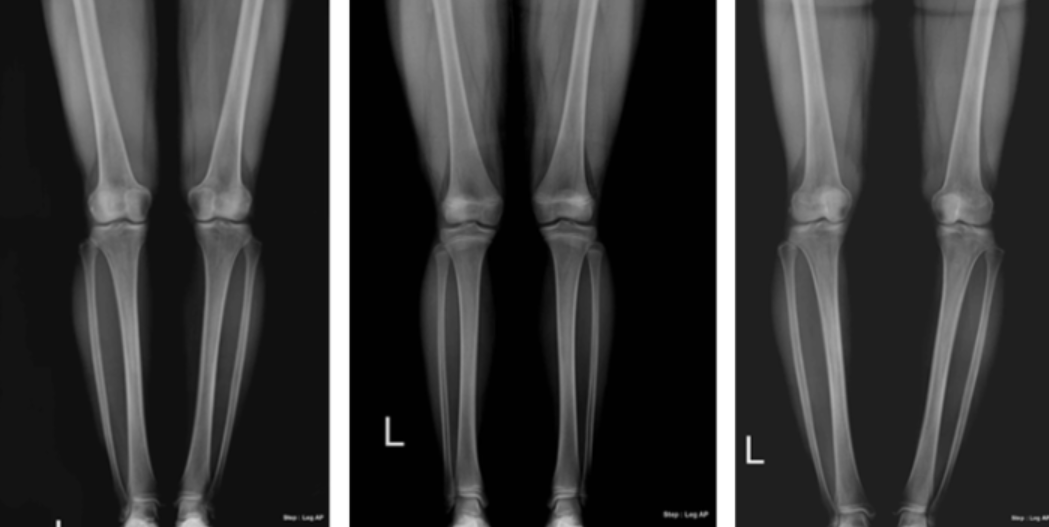

0다리 ㅣ X다리 개선

오다리 증상

- 무릎 사이에 주먹이 들어가는 경우

- 신발이 안쪽 또는 바깥쪽 부위만 과도하게 닳는 경우

- 치마를 입었을 때 돌아가는 경우

- 좌우 엉덩이 높이가 서로 다른 경우

- 한쪽 어깨가 올라가 있는 경우

- 다리를 꼬고 앉는 것이 더 편한 경우

엑스다리 증상

- 바르게 서 있을때 무릎이 붙어 있고 종아리가 벌어져 있는 경우

- 무릎이 자꾸 부딪혀 넘어지는 경우

- 무릎이 불편한 경우